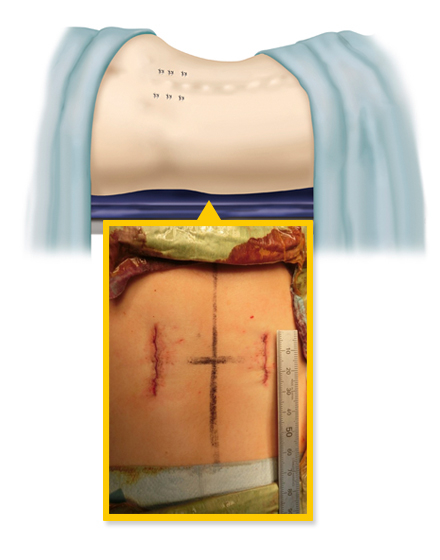

低侵襲経椎間孔的椎体間固定術 MIS-TLIF (エムアイエスティーリフ)

従来の腰椎の後方除圧固定術は、背部に約10~15cm程度の切開を加え手術を行っておりましたが、当院では、皮膚切開を最小限に抑え(通常は約4~5cm程度の創)神経除圧と椎間板切除、人工骨の充填を行います。その後、約2cmの皮膚切開を別に2カ所ほど加えて、レントゲンを見ながら金属スクリューを安全に刺入します。この手術の利点は、筋肉の損傷を最小限にして、出血量低減、術後疼痛の軽減、早期離床、早期退院、早期社会復帰を可能とすることです。手術は2時間から3時間ぐらいで、翌日から起立、歩行が許可されます。入院期間は通常14日間程度になります。